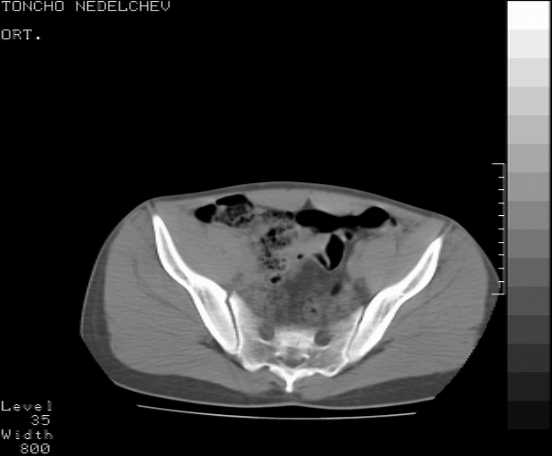

[Ortho] Acetabular fracture

Here are some more axial images. What is your opinion as for the timing of the operative treatment?